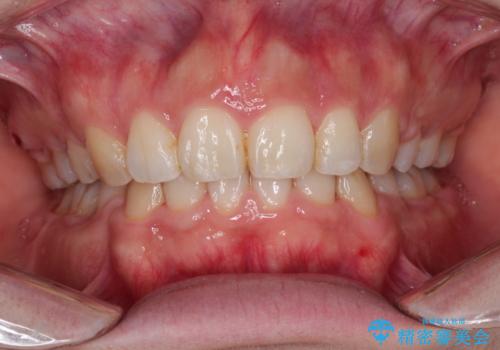

40代女性 前歯の重なり あきらめずに矯正

セラミックと矯正を併用してきれいな前歯へ